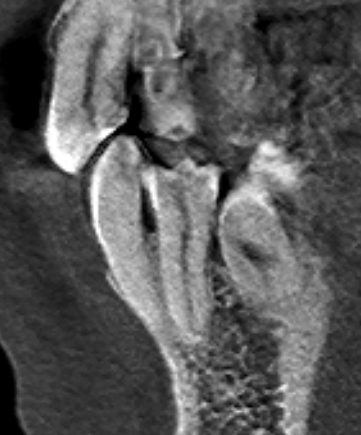

Александр9 Опубликовано 26 ноября, 2021 Поделиться Опубликовано 26 ноября, 2021 Мне предлагают удалить дистопированный 35 зуб, но он мне не мешает. Меня только пугает, что из-за него "страдают" соседние зубы. И если его не удалить, то со временем придется удалять и их. Подскажите пожалуйста, оправданно ли его удаление с целью улучшения "жизни" соседних 34, 36 зубов? (при условии нормальной гигиены (ирригатор, зубные нити) и лечении кариеса). Ссылка на комментарий